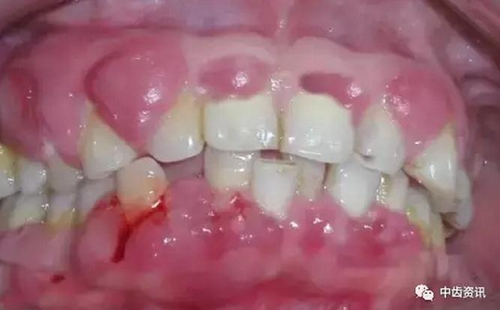

毛狀白斑是發(fā)生于舌兩側(cè)邊緣的白色或灰色的病變,病變也可延伸到舌腹部及舌背部,不能擦除。毛狀白斑在HIV感染及艾滋病患者中,是發(fā)生率僅次于念珠菌病的常見的口腔表征,也是HIV相關(guān)疾病的標志,幾乎僅見于HIV感染和艾滋病人人群,有非常顯著的特異性。因此,對毛狀白斑的出現(xiàn)應(yīng)予以高度重視。 牙周病表現(xiàn)為牙齦發(fā)炎、牙齦潰瘍、牙齦壞死以及牙齒松動,并可出現(xiàn)牙齦出血疼痛和惡變等癥狀。

2.jpg

據(jù)報道,19%~29%的HIV感染或艾滋病患者有牙周炎。 卡波濟肉瘤呈單個或多個紅色、淡藍色或紫色的斑塊或腫塊,有或無潰瘍,先見于上腭和牙齦,卡波濟肉瘤在一般人群中很罕見,隨艾滋病的發(fā)展,卡波濟肉瘤大量出現(xiàn)于艾滋病危險人群中。在美國,艾滋病患者患卡波濟肉瘤的可能至少比一般人群大2萬倍。在HIV感染者和艾滋病患者的口腔表征中,卡波濟肉瘤的患病率僅次于念珠菌病和毛狀白斑,具有較高的發(fā)生率。" 一些流行病學(xué)資料顯示,所有HIV陽性者或艾滋病患者,從嬰幼兒至成年人,均可發(fā)生口腔損害。通常發(fā)病率最高的人群為男性同性戀患者、異性戀者、靜脈注射毒品者等成年人。